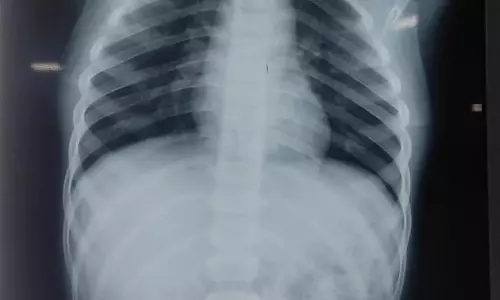

சிறுவனின் உணவு குழாயில் சிக்கியிருந்த நாணயங்கள் அறுவை சிகிச்சையின்றி அகற்றம்

திருவண்ணாமலை அரசு மருத்துவமனையில் சிறுவனின் உணவு குழாயில் சிக்கியிருந்த நாணயங்கள் அறுவை சிகிச்சையின்றி அகற்றப்பட்டது.